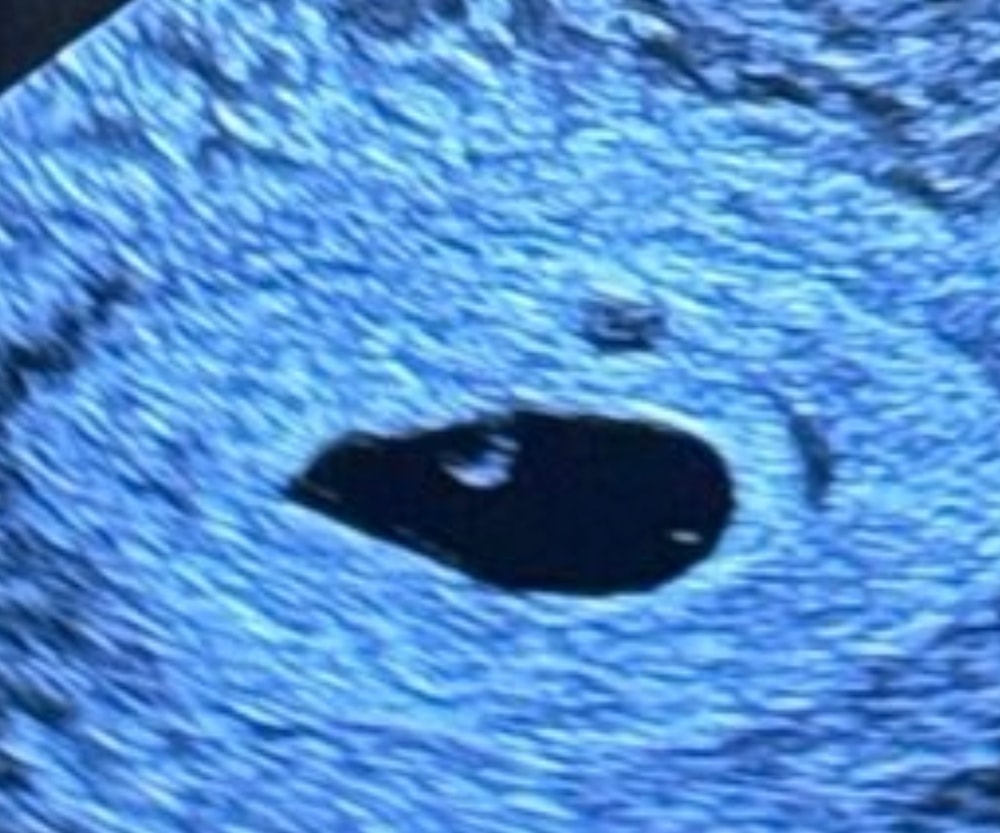

Срок 5+2 жм есть, эмбриона пока нет

УЗИ, КТГ, доплерЗдравствуйте, была на узи, сказали пя 11 мм жм 3мм, эмбрион пока не визуализируется. Это норм для такого срока? Рассматриваю узи и пытаюсь найти хоть намек на эмбриональный полюс. Или ещё рано и успокоиться?

В 5 недель далеко не у всех есть эмбрион и сб. У меня были беременности только с пя до 10-15 мм в 5 недель . Была одна с пя 21 мм в 5,2 нед, ктр 2 и сб. Но это скорее исключение.